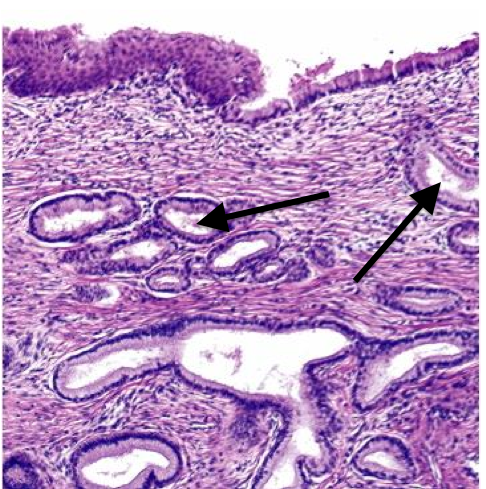

What tissue is this?

Adrenal gland - cortex

44

What tissue is this?

Adrenal gland - medulla